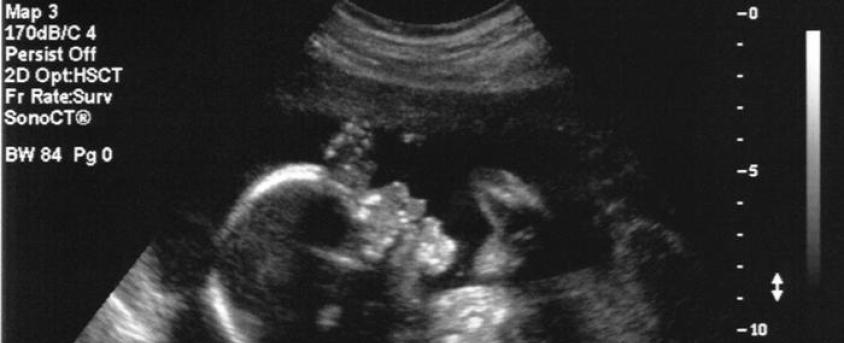

Apparently, the surgery was the first of its kind and was done to fix a rare condition where the baby’s skull wasn’t properly closing, which put pressure on the brain. The doctors were able to safely operate on the fetus while still in the womb, and both the mother and the baby are doing great.

The procedure is a huge leap forward in medical advancements, and it’s amazing to see what our technology and knowledge can do. It’s also incredible to think about how this could potentially give babies a better chance at a healthy life.